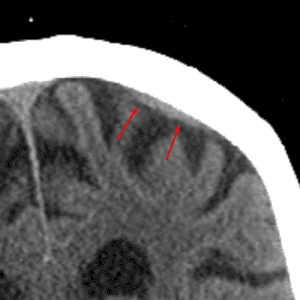

Cortical Vein

Mimicking extra-axial hemorrhage